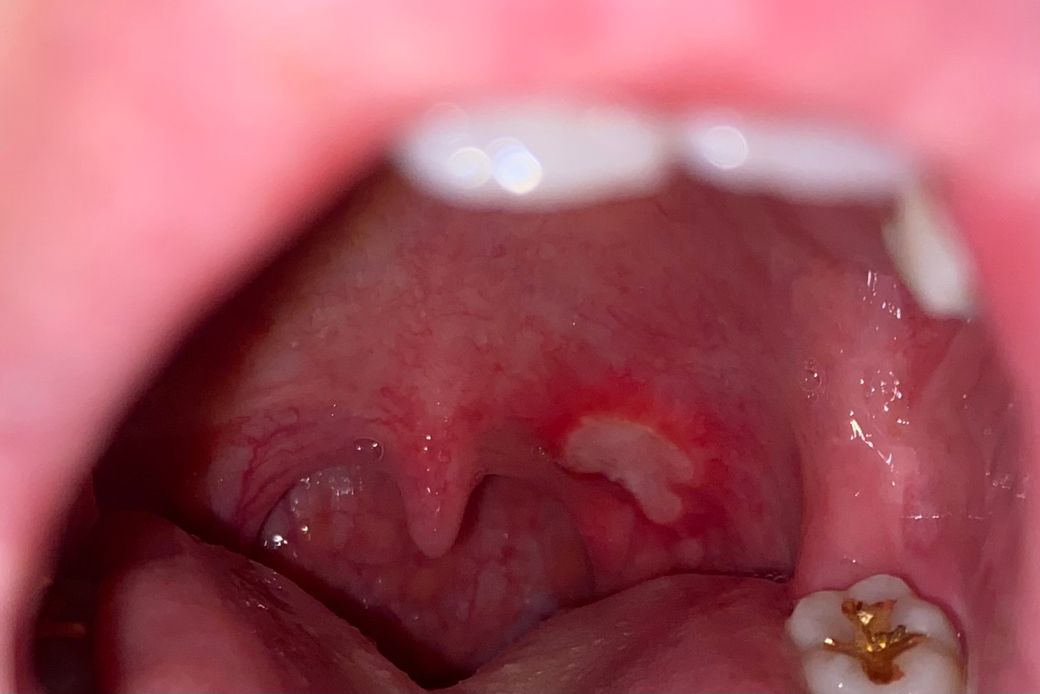

목젖 옆 구내염이 너무 크고 고통스러운데 구강암인가요

생긴지 5-6일쯤 되었고 점점 커지는듯하다가 어제부터는 크기를 유지하고있는데, 혀나 볼에 생겼던 구내염의 고통과는 너무 다릅니다. 생긴 위치때문인지 침이 계속 닿아서 그런지 더 쓰라리고 붓고 열감이 있습니다... 말을 할 때도 아픕니다.

진통제를 먹으면 훨씬 낫긴 합니다만 이렇게 큰 구내염을 처음 겪어서 걱정됩니다.

구강암으로 의심될 모양이나 소지가있는지 궁금합니다.

사진 순서대로, 마지막 제일 큰 모양이 가장 최근 사진입니다.

목젖 옆 구내염이 너무 크고 고통스러운데 구강암인가요-> 사진상으로는 단순 구내염인 것으로 판단됩니다.

구내염의 경우 최대한 자극이 가지 않도록 하셔야됩니다. 구강암은 아니니 일단 약을 구매 하셔서 바르시고 뜨겁거나 자극적인 음식은 당분간 피해주세요.

악성병소의 유무는 구강내과에서 조직검사를 진행해봐야 할 것 같습니다

대학치과병원의 구강내과 내원해보시기 바랍니다.

구강암은 아닌 것으로 보이며, 해당부위 통증 및 염증완화를 위해 탄툼가글액으로 가글하여 관리를 하고, 구내염개선에 도움이 되는 고함량 비타민비군 섭취와 충분한 휴식을 권합니다.